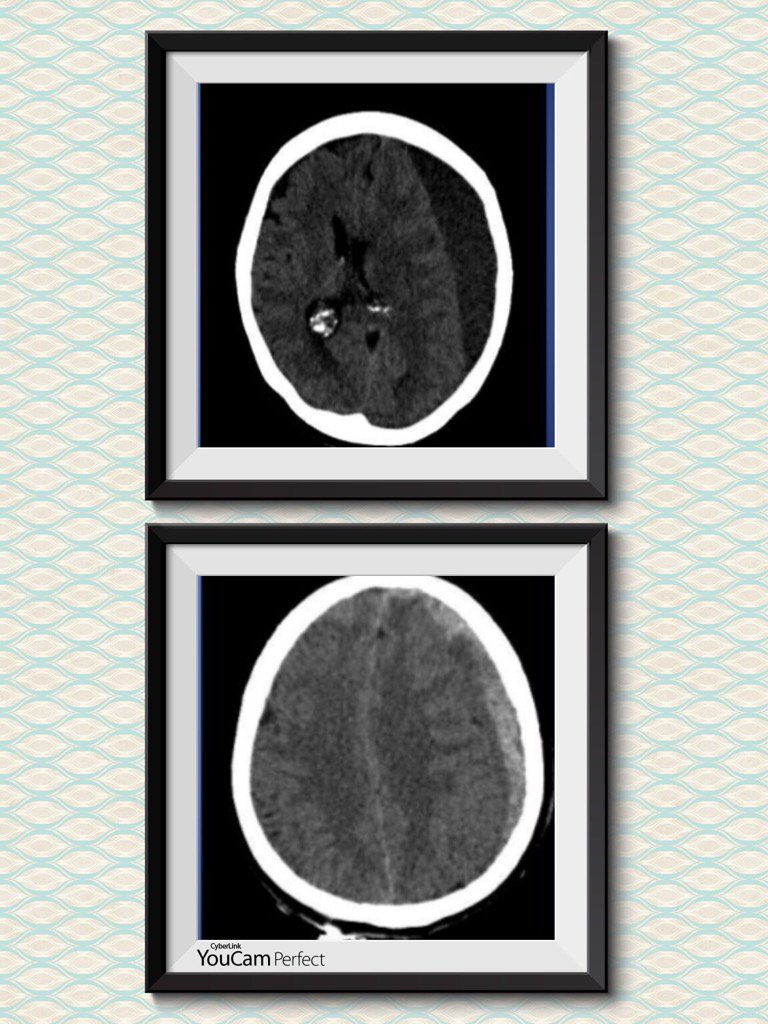

Hematoma subdural

Forma de mitja lluna, segueix el contorn del crani, superior

HSD crònic

l'inferior és subagut